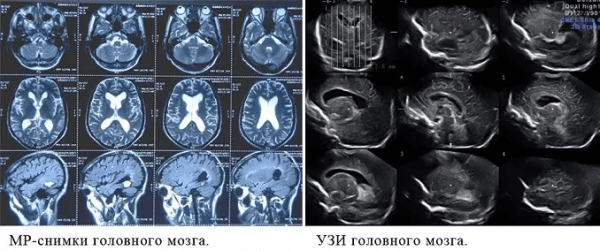

МРТ или УЗИ: что лучше и чем отличаются?

Современные методы инструментальной диагностики отличаются информативностью, безопасностью и неинвазивностью. Однако каждый из видов имеет определенные показания и противопоказания к проведению. Чтобы получить максимум диагностической информации, важно правильно выбрать необходимый метод, который имеет уникальный принцип действия и обладает разной способностью к дифференциации тех или иных структур. Чтобы разобраться в вопросе, что лучше МРТ или УЗИ, стоит рассмотреть принцип действия оборудования и ситуации, когда показан тот или иной вид диагностики.

Чем отличается МРТ от УЗИ?

Ультразвуковое исследование основано на способности ультразвуковых волн, испускаемых аппаратом, достигать «зоны интереса» и отражаться от нее. Разные по строению ткани обладают разной отражающей способностью. Именно это правило объясняет, почему при ультразвуковом сканировании формируются уникальные изображения в серо-шкальном спектре. Ткани с более плотной структурой сильнее задерживают эхо-сигнал, по этой причине тень от костных структур может нарушать визуализацию глубже расположенных тканей. Это ограничивает диагностическую ценность метода. С помощью УЗИ лучше удается изучить строение мягко-тканных образований, которые расположены примерно в 10-15 см от датчика. Ультразвуковая диагностика используется в изучении почек, печени, желчного пузыря, органов малого таза, сердца, крупных сосудов и т.д.

МРТ основана на явлении ядерного-магнитного резонанса, которое было открыто учеными в 1938 году. Оно заключалось в том, что ядра некоторых атомов, находясь в магнитном поле, под действием электромагнитного излучения способны поглощать энергию. Как известно из курса физики, поглощенная энергия никуда не девается, а один ее вид превращается в другой. В данном случае атомы испускают поглощенную энергию в виде радиосигнала. В этом и состоит разница того, чем отличается МРТ от УЗИ. Воздействие на тело человека переменного магнитного поля заставляет переходить атомы на более высокий энергетический уровень. А как только прекращается действие внешнего «магнита», протоны (именно на эти частицы настроены современные томографы) возвращаются на прежний энерго-уровень. Процесс возврата сопровождается резонансным выделением энергии. Разные по структуре ткани по-разному реагируют на магнитное поле, поэтому получаются четко дифференцируемые «картинки».

Есть некоторые органы, обследование которых рекомендуют начинать с проведения МРТ. В частности, речь идет о головного мозге. С помощью УЗИ оценить его строение у взрослых очень проблематично, т. к. со всех сторон мозг заключен в череп, который практически не пропускает ультразвуковых волн. Для МРТ это не является препятствием.